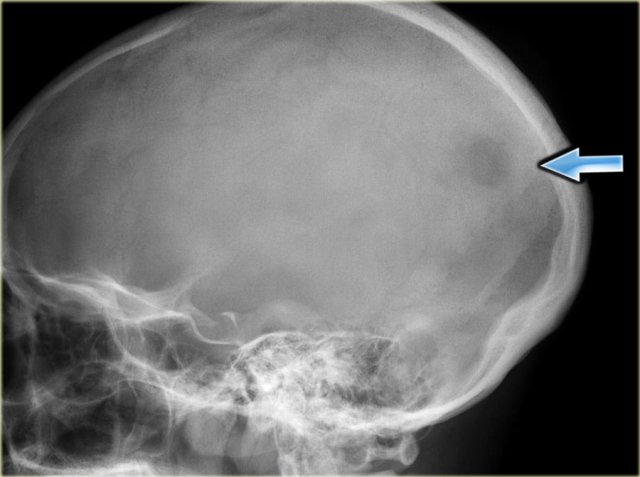

On the left a typical presentation of EG in the skull as an ill-defined osteolytic lesion.